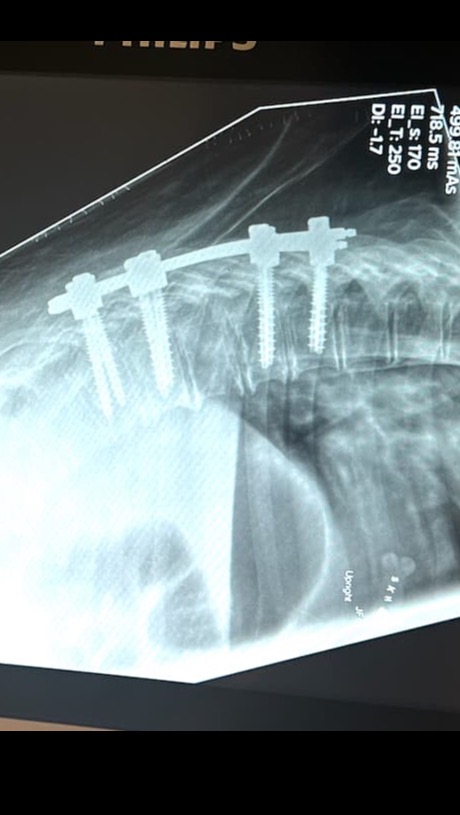

Tyler broke his Hip, Elbow, (bone is sticking out ) and he Broke his vertebrae T7-T11

he has had his surgeries on his spine, hip and elbow.